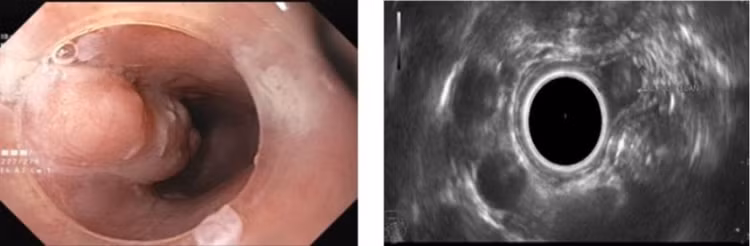

Đó là trường hợp bệnh nhân nữ 37 tuổi trú tại phường Hà An, TX Quảng Yên, Quảng Ninh. Gần đây, bệnh nhân có cảm giác nuốt vướng, nuốt nghẹn nên đến khám tại Bệnh viện Bãi Cháy. Các bác sĩ đã chỉ định nội soi thực quản dạ dày và phát hiện một khối u dưới niêm mạc kích thước lớn với chiều dài lên đến 3cm nằm ở 1/3 trên thực quản. Bệnh nhân ngay sau đó được thực hiện siêu âm nội soi (EUS).

Đây là kỹ thuật tiên tiến, hiện đại trong nội soi có thể xác định được cấu trúc u cũng như vị trí xuất phát u trong thành ống tiêu hóa. Khối u của bệnh nhân được xác định là tổn thương giảm âm nằm ở lớp thứ 2 của thành thực quản.

Hình ảnh khối u trên nội soi ánh sáng trắng và siêu âm nội soi - Ảnh BVCC

Đánh giá khối u kích thước lớn gây nên các triệu chứng khó chịu cho người bệnh, tuy nhiên khối u nằm ở lớp thứ 2 của thành thực quản và còn cơ hội can thiệp cắt bỏ qua nội soi mà không cần phải phẫu thuật.